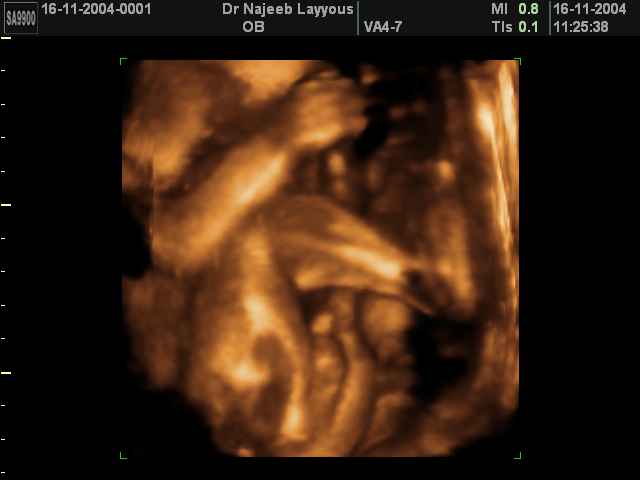

- Fetal Parts Ultrasound Scan Photos